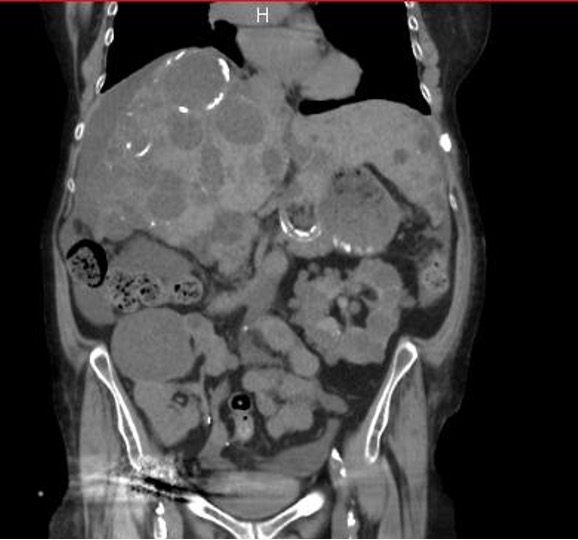

Given the inability to obtain vascular access, the patient was offered PD. The catheter was placed laparoscopically, and a hernia repair of the linea alba was performed simultaneously. At the time of PD, the patient’s weight was 53 kg for 1.66 m, and the residual diuresis was 1500 ml/24 h. The abdominal computed tomography (CT) scan of the patient at that time is shown inFigure 1..

Figure 1.Abdominal CT scan shows the large hepatomegaly, the residual native kidney on the left, and the dysfunctional renal graft in the right iliac fossa